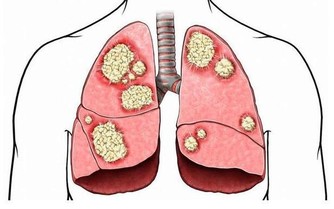

要想寶寶的視力健康發展,家長們可別等到發現問題再去看,那可就晚啦!專家的意思是,寶寶視力篩查應該從“0”開始,一些新生兒出生後便患有先天性白內障、眼部惡性腫瘤等眼部疾病,而且6歲之前的許多眼病,都可能影響視力發育。所以從寶寶一出生就應該做眼睛的健康篩查,寶寶眼病要早發現、早治療。